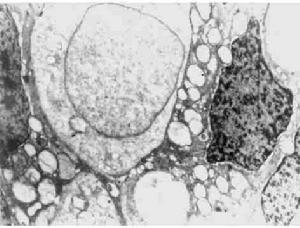

症狀卵巢類癌的大體觀是畸胎瘤中具有黃色實性結節,直徑3~15cm,平均9cm。鏡下瘤細胞大小一致,來自中腸的類癌細胞排列成島狀或巢狀;來自前腸和後腸的類癌癌細胞排列成小樑或花帶狀。電鏡下島狀類癌癌細胞的神經分泌顆粒不規則成啞鈴狀,而小樑花帶狀類癌的神經分泌顆粒為圓形或卵圓形

甲狀腺腫類型的瘤細胞排列成小梁、島狀或混合型。類癌和甲狀腺組織混雜存在。類癌細胞有親銀和嗜銀2種。免疫組織化學染色甲狀球蛋白及神經內分泌細胞標記均為陽性。電鏡下可找到圓形或卵圓形的神經內分泌顆粒,直徑為100~400nm。